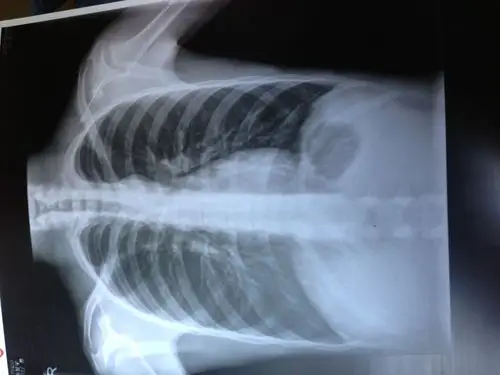

休息后疼痛没有减轻,来我院就诊,经查体拍片诊断为胸12椎体压缩性骨折